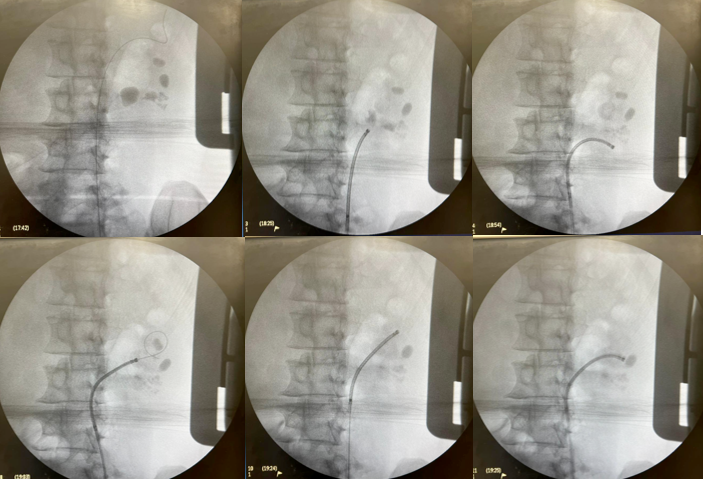

Sequência do tratamento:

-Tempo cirúrgico – 94 minutos

-Alta no 1oPO

-Retirada do Duplo J no 7o PO

-Eliminou vários pequenos fragmentos

-TC com 30 dias – livre de cálculo